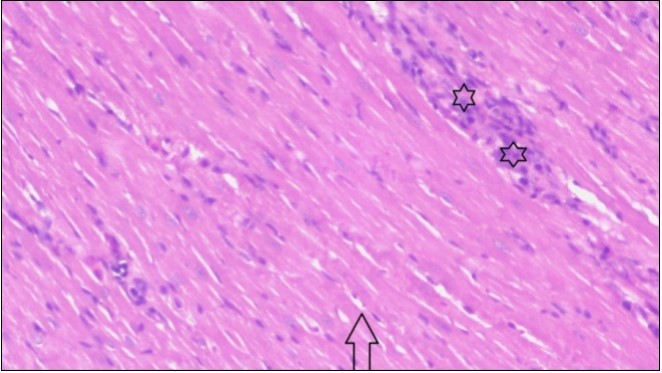

An important organ that is affected directly by the obesity which is the heart: The heart is the main important organ in circulatory system, the heart wall has three basic layers; the tunica intima of the heart is called endocardium, the tunica media of the heart is called the myocardium, the tunica adventitia of the heart the epicardium. The histological examination of the hearts of control rats feeding standard diet showing normal cardiac tissue with elongated, unbranched multinucleated muscle fibers (arrow), (Figure 1). The rats are feeding (HFD) for 2 weeks (obese rats) showing large number of inflammatory cells (star), degeneration muscles fiber ,circle and congested Blood vessels (arrow) (Figure 2). By comparison hearts of rats are treated by fennel after obesity and control rats observed show improved cardiac tissue with less infiltration (star) and well organized elongated muscle fibers with peripheral nuclei (arrow) (Figure 3). While examination of rats heart that treated by ator after obesity appears show less improved cardiac tissue with few inflammatory cells between disorganized muscle fiber (star), (Figure 4). While combined hearts of rats are treated by fennel and ator after obesity and control mice are showing nearly cardiac tissue with well-organized muscles fibers (arrow), (Figure 5).

Figure 4.Photomicrograph of heart section of treated rat with Ator drug showing less improved cardiac tissue with few inflammatory cells between disorganized muscle fiber (star), (H&E) (400X).

Figure 5.Photomicrogragh of heart section of treated rat with both fennel herb and Ator drug showing nearly normal cardiac tissue with well-organized muscles fibers (arrow), (H&E) (400X).

These results were confirmed with histological changes of feeding rats heart tissues with high fat diet only, which showed vaculation of tunica media and narrowing in the lumen of aorta sections as well as congestion of cardiac blood vessel and hyalinosis of its wall. This result was confirmed by Szilvassy et al., 78, who indicated that although hyperlipidemia increases oxidative stress in the cardiovascular system, it renders the heart and the vasculature more susceptible to stress. Ouwens et al. 79 identified that development of hyper-cholestremia, which is one of the risk factors for cardio vascular diseases is associated with increased blood levels of TC, LDL-C and VLDL-C as well as lowered levels of HDL in rats fed on high fat-diet. This result was confirmed by histological study, which revealed apparent normal histological structure of heart in all treated rats with fennel seeds. Epidemiologic studies have shown an inverse correlation between HDL-C level and the risk of cardiovascular disease. Increasing the HDL cholesterol level by 1mg may reduce the risk of cardiovascular disease by 2 to 3 percent 80. The present data agreed with Fatiha et al. 81, who reported that hyper-lipidemic rats treated with fennel extract had significant decrease in plasma levels of TL, TG, TC, LDL-C and VLDL, and significant increase in HDL-C level. The current study demonstrates that the alteration induced by high fat diet causing changes in blood parameters. These changes are exhibited through a decrease in RBCs, Ht, Hb and platelet and these changes could be due to oxidative stress, which lead to lipid peroxidation in RBCs membranes, auto oxidation of hemoglobin. As regards the total WBCs, lymphocytes and monocytes showed a marked decrease. While a distinct increase in the percentage of neutrophils and esinophils. The present, demonstrates that rats treated with (fennel), (ator) and (fennel with ator) exposure provided significant protection to the altered haematological variables. The effect of the treatment with fennel and ator is more effective than fennel only or ator only. The current study showed that the serum levels of the total protein and albumin in the obese group were significantly higher than those of the control group. The administration of (fennel) revealed significant decrease in the serum levels of the albumin and total protein as compared to the obesity group, although the serum levels of the albumin and total protein of the Ator group less than the obesity group. Otherwise, the levels of the total protein and albumin in fennel and Ator group were near to the similar value of the control group. The finding of this study indicates that the concentration of Malondialdehyde (MDA) and Myeloperoxidase (MPO) in liver homogenates of the fennel and ator group significant decrease than group (3) and group (4) and obesity group. There is a growing awareness that obesity is a prime risk factor for the development of dyslipidemia profile and that oxidative stress may play a role in various adverse effects of obesity.